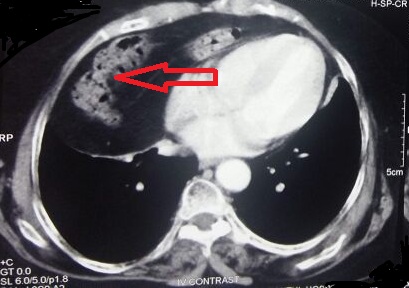

Eight decades of asymptomatic Morgagni Hernia

Morgagni hernia, diaphragmatic hernia, congenital herniaAbstract